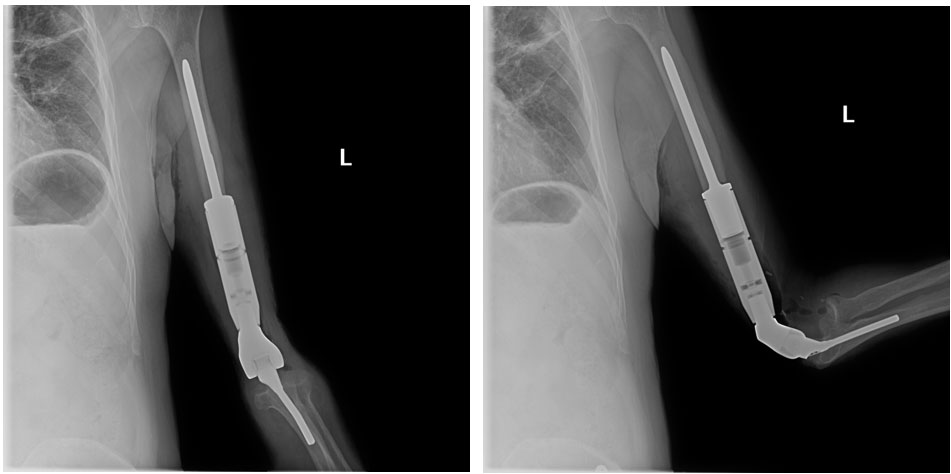

Ameliyat Sonrası: Röntgende çimentolu distal humerus protezi yerleştirilmiş olarak görülmekte.

Akciğer Kanseri Kol Kemiği Metastazı | Distal Humerus Protez Uygulaması